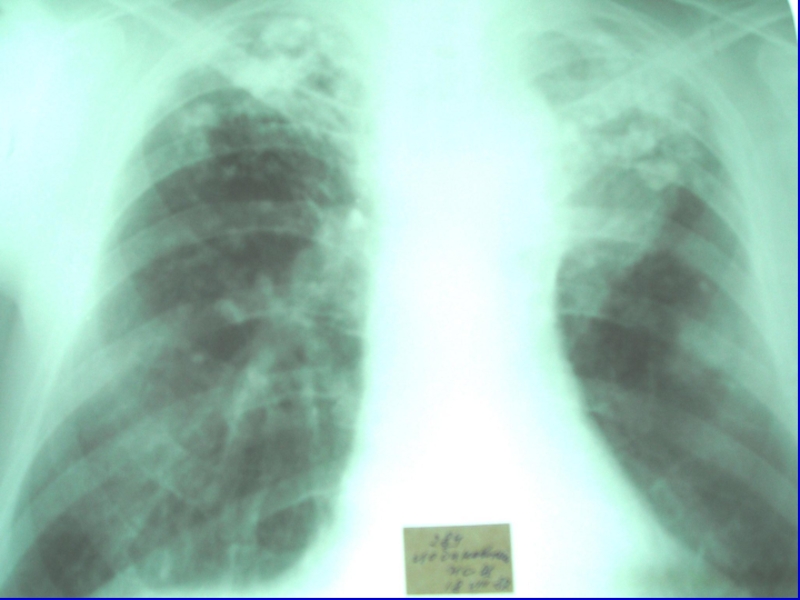

Слайд 23Рентгенологическая картина

Рентгенологически симметрично в обоих легких, преимущественно в верхних и

средних отделах, обнаруживаются в одних случаях однотипные средние, в других

– крупные очаги.

При крупноочаговых процессах определяются очаги до 1 см, округлой или неправильной формы без резких очертаний, в верхних отделах могут обнаруживаться отдельные или множественные тонкостенные (штампованные) каверны, которые в части случаев выявляются только при томографическом исследовании.

В редких случаях лимфогенного диссеминированного туберкулеза очаги располагаются в средних отделах на фоне выраженной сетчатой и линейной тяжистости. Корни легких и при гематогенной и лимфогенной диссеминации обычно нерезко расширены.